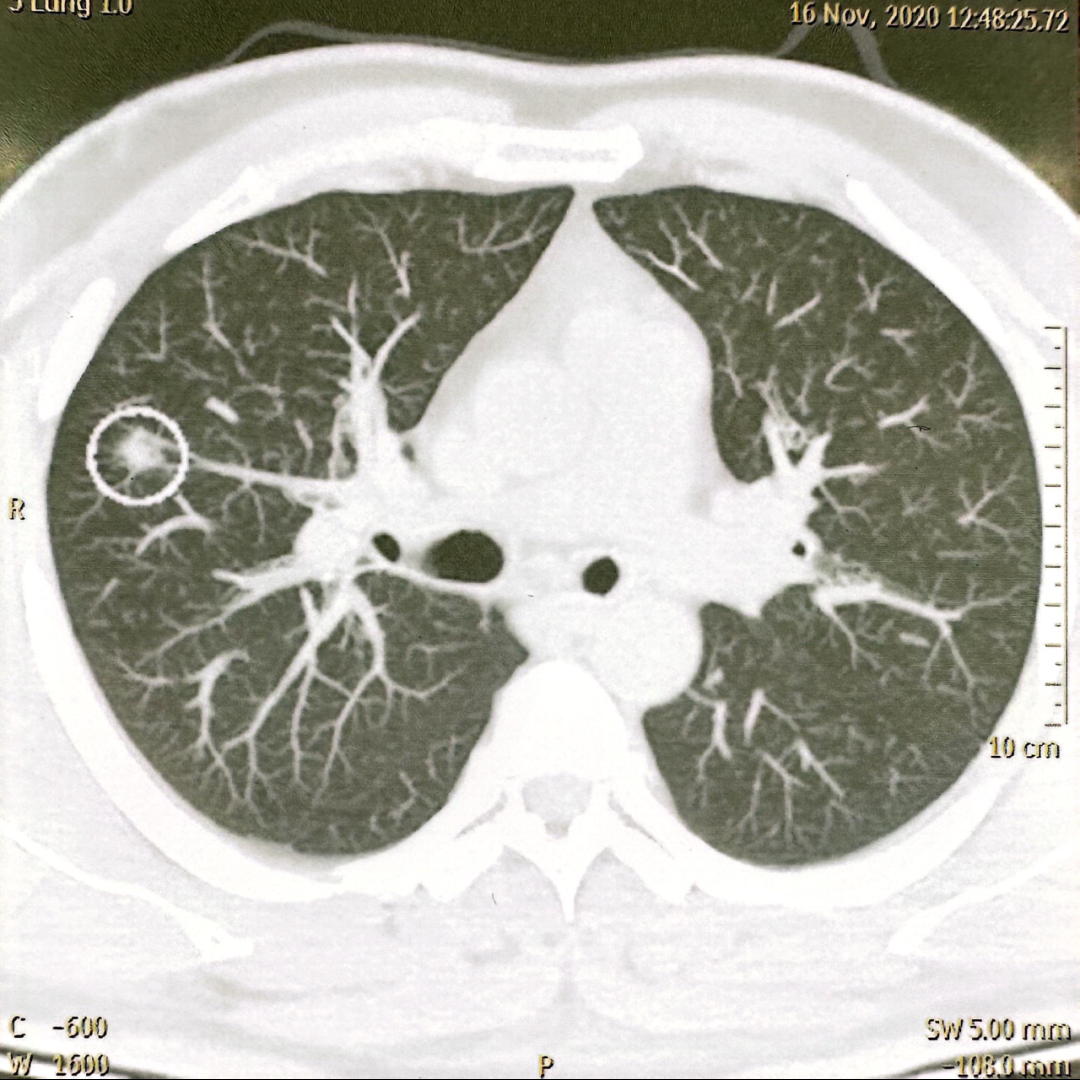

2020年冬天,在体检时,王先生被查出右肺上叶有个0.6厘米的微小结节——比一粒米大不了多少。经过多学科会诊后,考虑为肺原位癌,随即做了右肺上叶楔形切除手术。

西安市人民医院(西安市第四医院)胸科病院张艰教授,凭借30余年深耕肺癌精准诊疗的经验,接手了这个棘手的病例。她没有急于下结论,而是重新拿起王先生四年前的肺部CT,反复研读后发现,那个看似不起眼的0.6厘米结节,可能是浸润性腺癌。